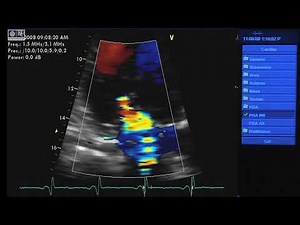

2:28

Measure PISA in Mitral Regurgitation

22.6K views

May 22, 2021

YouTube

bashir motwli